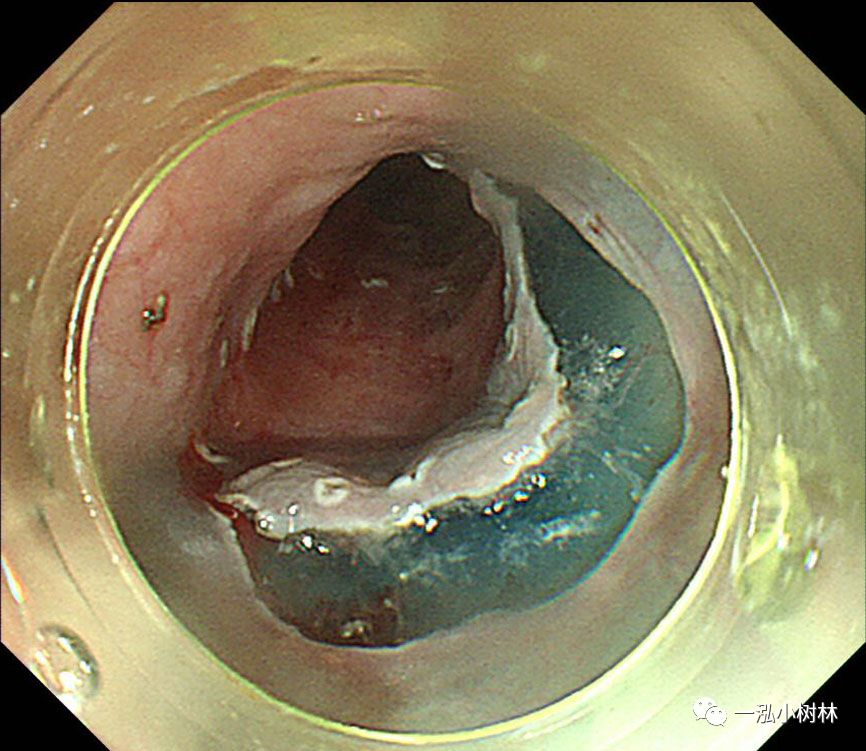

图8 行左侧黏膜下剥离术。在重力的作用下,黏膜剥离(左侧卧位行ESD)

图9 在标本的背面进行钛夹牙线牵引